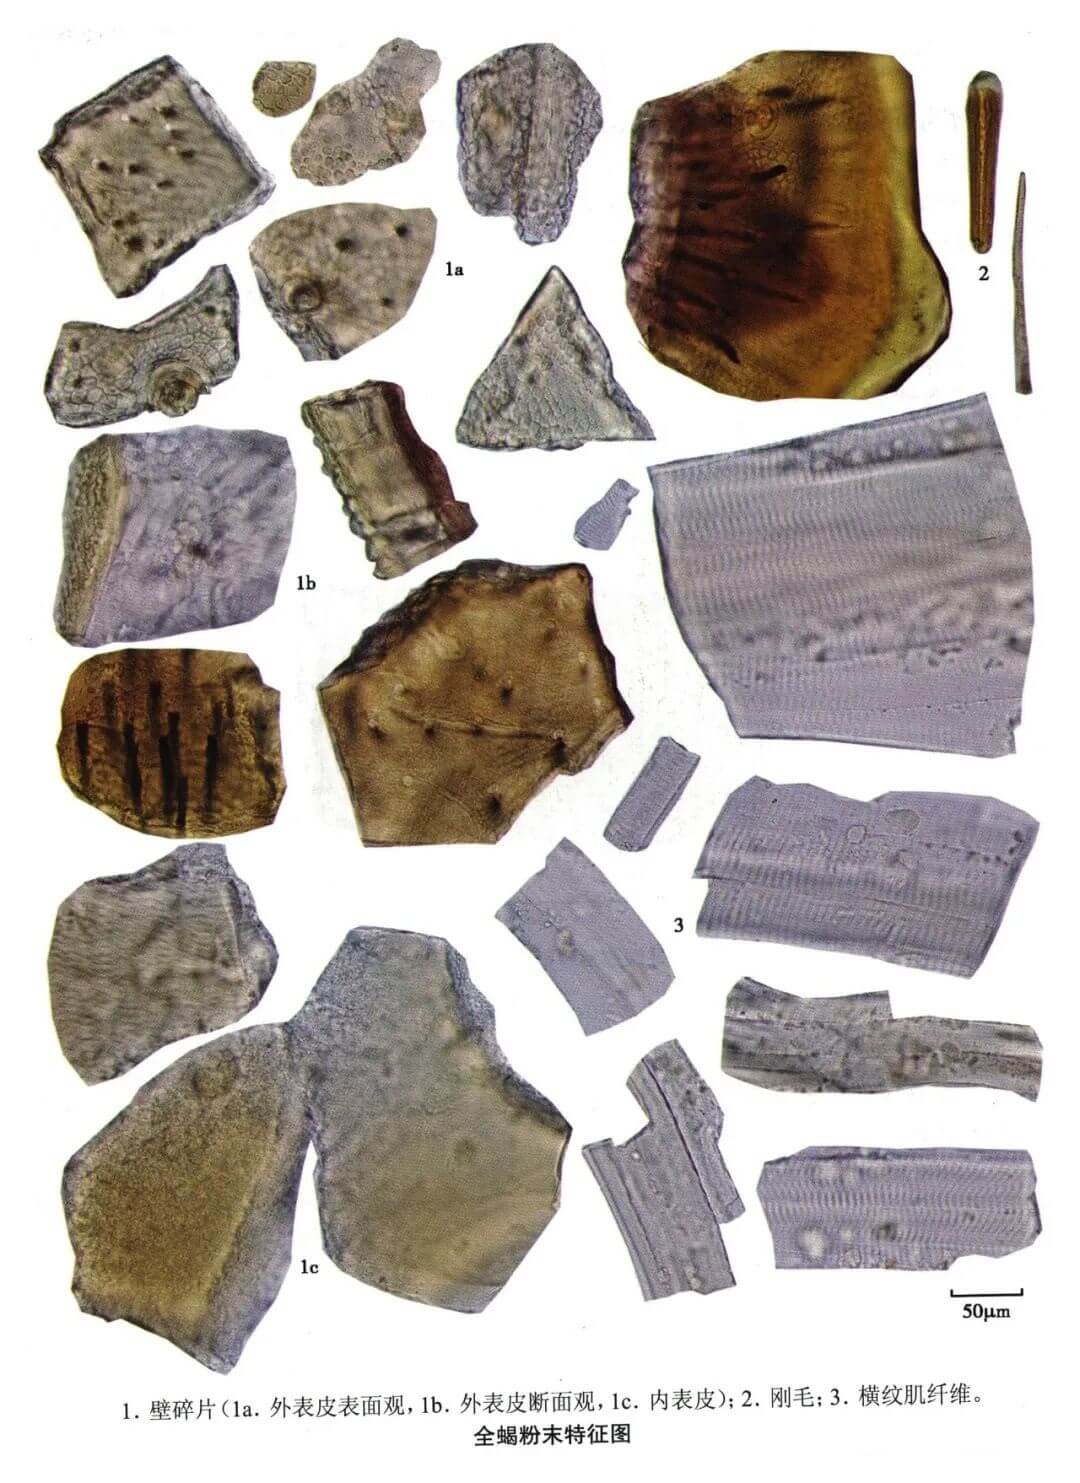

全蝎

| 全蝎 |

|---|

| 【参考标准】 《中国药典》2020年版 一部 |

| 【显微鉴别】 本品粉末黄棕色或淡棕色。体壁碎片外表皮表面观呈多角形网格样纹理,表面密布细小颗粒,可见毛窝、细小圆孔和淡棕色或近无色的瘤状突起;内表皮无色,有横向条纹,内、外表皮纵贯较多长短不一的微细孔道。刚毛红棕色,多碎断,先端锐尖或钝圆,具纵直纹理,髓腔细窄。横纹肌纤维多碎断,明带较暗带宽,明带中有一暗线,暗带有致密的短纵纹理。 |

| 【显微重点】 体壁碎片可见毛窝;刚毛;横纹肌纤维具有明暗条带。 |

| 【图谱来源】 《中药成方制剂显微图典》 |